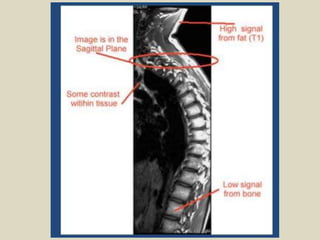

Magnetic resonance imaging (MRI) was discovered in 1947 by two physicists and the first clinical images were obtained in 1977. MRI uses strong magnetic fields between 1-9 Tesla to align hydrogen atoms in the body and radio waves to elicit signals to form images. The document provides a brief history of MRI and discusses magnetic fields, relaxation processes, and pulse sequences used to generate MRI images.